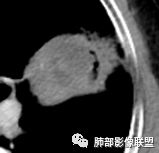

左肺上叶类圆形软组织影,边界较清楚,其内密度均匀,外侧缘可见空气新月征,并可见点状钙化,增强扫描可见均匀强化,病灶周围可见磨玻璃渗出性密度影,斜裂侧光滑平整。考虑炎性病灶,以肉芽肿性炎症为主(如真菌性肉芽肿),鉴别结核(无卫星灶,无多态性),肺癌(无毛刺,分叶等恶性征象,)细菌性炎症(密度一般不这么致密,很少钙化及空气新月征)。

胸部CT:左肺上叶类圆形肿块影,边界较清楚,密度较均匀,内可见小片坏死、偏心空洞、空气新月征、点状钙化,周围晕、絮状渗出、边缘模糊,支气管扩张、充气征、支气管进入病灶堵塞,叶裂牵拉明显,增强扫描中度均匀强化,纵隔可见淋巴结。考虑:炎性病灶,肉芽肿性炎症,曲霉?毛霉?鉴别:TB,淋巴瘤。

左上肺类圆形肿块影,边界较清楚,支气管通畅略扩张,周围磨玻璃影,其内密度均匀,外侧见空气新月征,且见点状钙化。叶间裂光滑稍膨隆。老年男性,糖尿病,高血压,痰培养克雷伯菌。综合考虑炎性病灶,克雷伯合并真菌感染,曲霉。结核合并真菌。鉴别肺癌合并感染。

左肺上叶类圆形软组织影,边界稍模糊,其内密度均匀,外侧缘可见空气新月征,并可见点状钙化,增强扫描渐进性强化,病灶周围可见磨玻璃影,斜裂侧光滑平整,气管未见明显闭塞,淋巴结未见肿大,糖尿病患者,首先考虑感染性变,结核并曲霉?